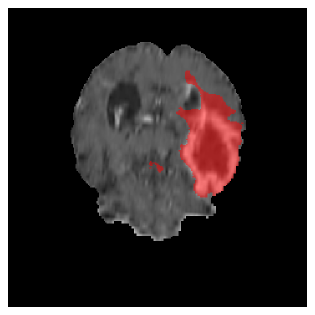

Appendix A Qualitative results

Figures 4 and 5 present the segmentation results for a patient from the BRATS dataset, visualized on a randomly selected slice. Figure 4 illustrates how tumor segmentation evolves over multiple episodes in S1 across different approaches including cumulative, naive, our approach, and the best buffer-free strategy (SI, =2). The cumulative approach, which trains on all encountered datasets together, maintains segmentation consistency across episodes but introduces significant amounts of false positives, particularly in the upper left area of the brain images. These misclassifications highlight its inability to generalize well across datasets despite access to all previous data. The naive approach, which learns sequentially without any continual learning strategy, suffers from severe catastrophic forgetting. While it initially segments well, performance deteriorates over episodes, leading to a near-complete loss of segmentation capability by the final episode. The SI (=2) approach, a regularization-based buffer-free CL strategy, performs reasonably well in early episodes but shows a significant performance decline over time. By the last episode, much of the tumor was no longer segmented, indicating difficulty in retaining prior knowledge. In contrast, our proposed approach initially produces more false positives but progressively refines its segmentation. By the final episode, it accurately retains the tumor region while minimizing misclassifications, demonstrating strong knowledge retention and adaptability across episodes. This suggests that our approach effectively mitigates catastrophic forgetting while maintaining segmentation performance over sequential learning.